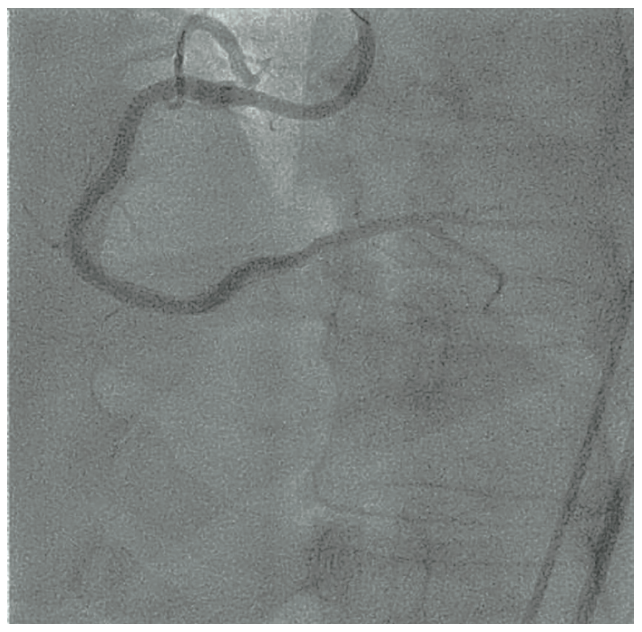

For dual coronary injection, an 8 French (Fr) arterial sheath in the right femoral artery and a 6 Fr arterial sheath in the left femoral artery were inserted. An 8 Fr Amplatz Left 0.75 guide catheter was used to engage the RCA and a 5 Fr Judkins Left 4 diagnostic catheter engaged the left coronary artery (LCA). A Pilot 200 (Abbott Vascular) guidewire was initially used unsuccessfully, followed by a MiracleBros 6 (Asahi Intecc) guidewire, which crossed the CTO and was placed in the right posterolateral (RPL) branch (Figure 2). A BMW guidewire replaced the Miraclebros guidewire through an over-the-wire balloon. After multiple high-pressure balloon inflations of all RCA segments, there were still difficulties with delivering a stent to the RPL. A two-GuideLiner (GL)(Teleflex) technique (“mother-daughter-granddaughter” system) was used to maximize the support (a 6 Fr GL in an 8 Fr GL through an 8 Fr Amplatz Left catheter, Figure 3).9,10 A 2.25 mm x 30 mm Resolute stent (Medtronic) was implanted in the RPL branch. A 3 mm x 22 mm Resolute stent and a 3 mm x 30 mm Resolute stent were implanted distal to the proximal RCA, but there was a very high resistance noted upon advancement of the stents. There was also resistance to pulling out the last stent balloon and BMW guidewire, which had to be pulled out together as a unit. During this process, the BMW wire fractured at the junction of the distal tip and shaft. Fortunately, the fractured BMW segment was within 2 GLs; thus, these were removed together with the wire and the balloon without further complications (Figure 4). The final result of the PCI was satisfactory (Figure 5).

The ideal management of fractured guidewires includes removal percutaneously or surgically. Stent implantation over the guidewire remnants may be an acceptable option if retrieval is not successful. This case illustrates the complexity of modern PCI that comes with the potential price of equipment failure. Not only did we “push the limits” of the guidewire that fractured, but we also set up a very powerful PCI support system, which resulted in successful stent delivery. This setup fatigued the guidewire to the point of fracturing, yet allowed for retrieval of the broken wire.